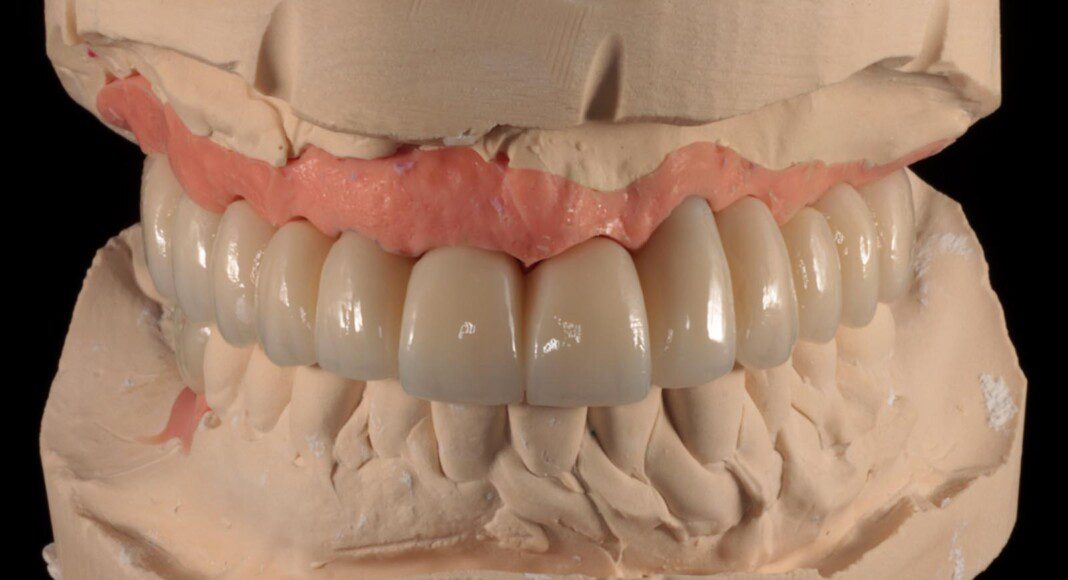

Prototype try-in. This patient was much more particular than we expected. Therefore, we made a very detailed prototype for everyone to evaluate closely. Pictures taken from all angles.